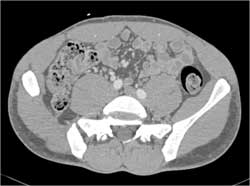

Cellulitis